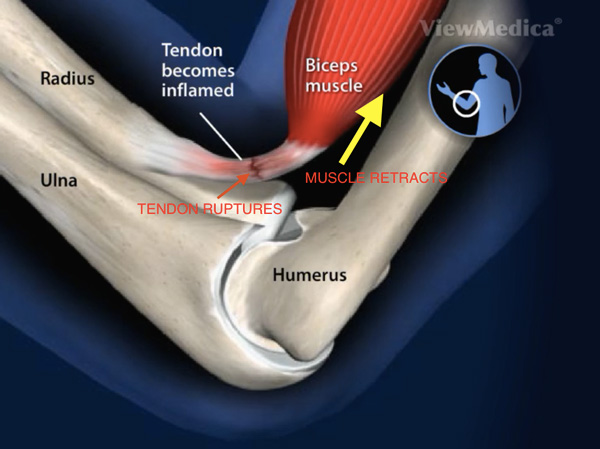

Proximal Biceps Tendon Rupture Popeye Deformity Everything You Need To Know Dr. Nabil Ebraheim

Biceps Tendon Tear at the Elbow OrthoInfo AAOS